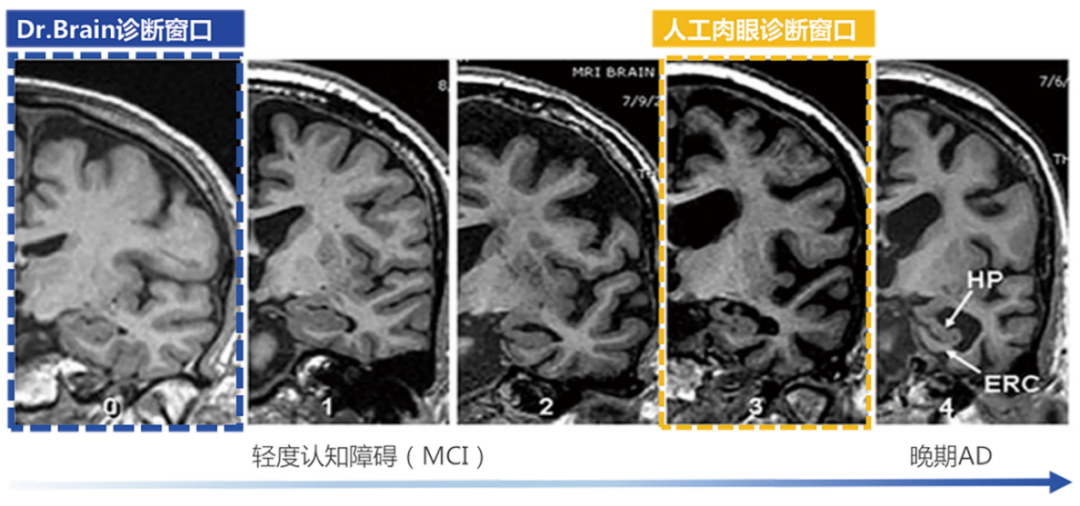

超早期的診斷

利用AI算法識別肉眼難以發(fā)現(xiàn)的腦結(jié)構(gòu)超早期的細微改變,大幅提前疾病診斷窗口